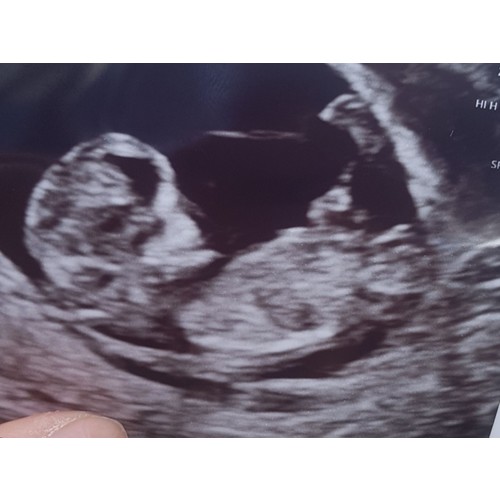

Wat een mooie manier! Iemand die dit bij onze frummel ook kan ontdekken?

Wat denken jullie meisje of een jongetje.. spannend!

Jongen denk ik, ook de nub馃挋

Wat denk je van mijne ?